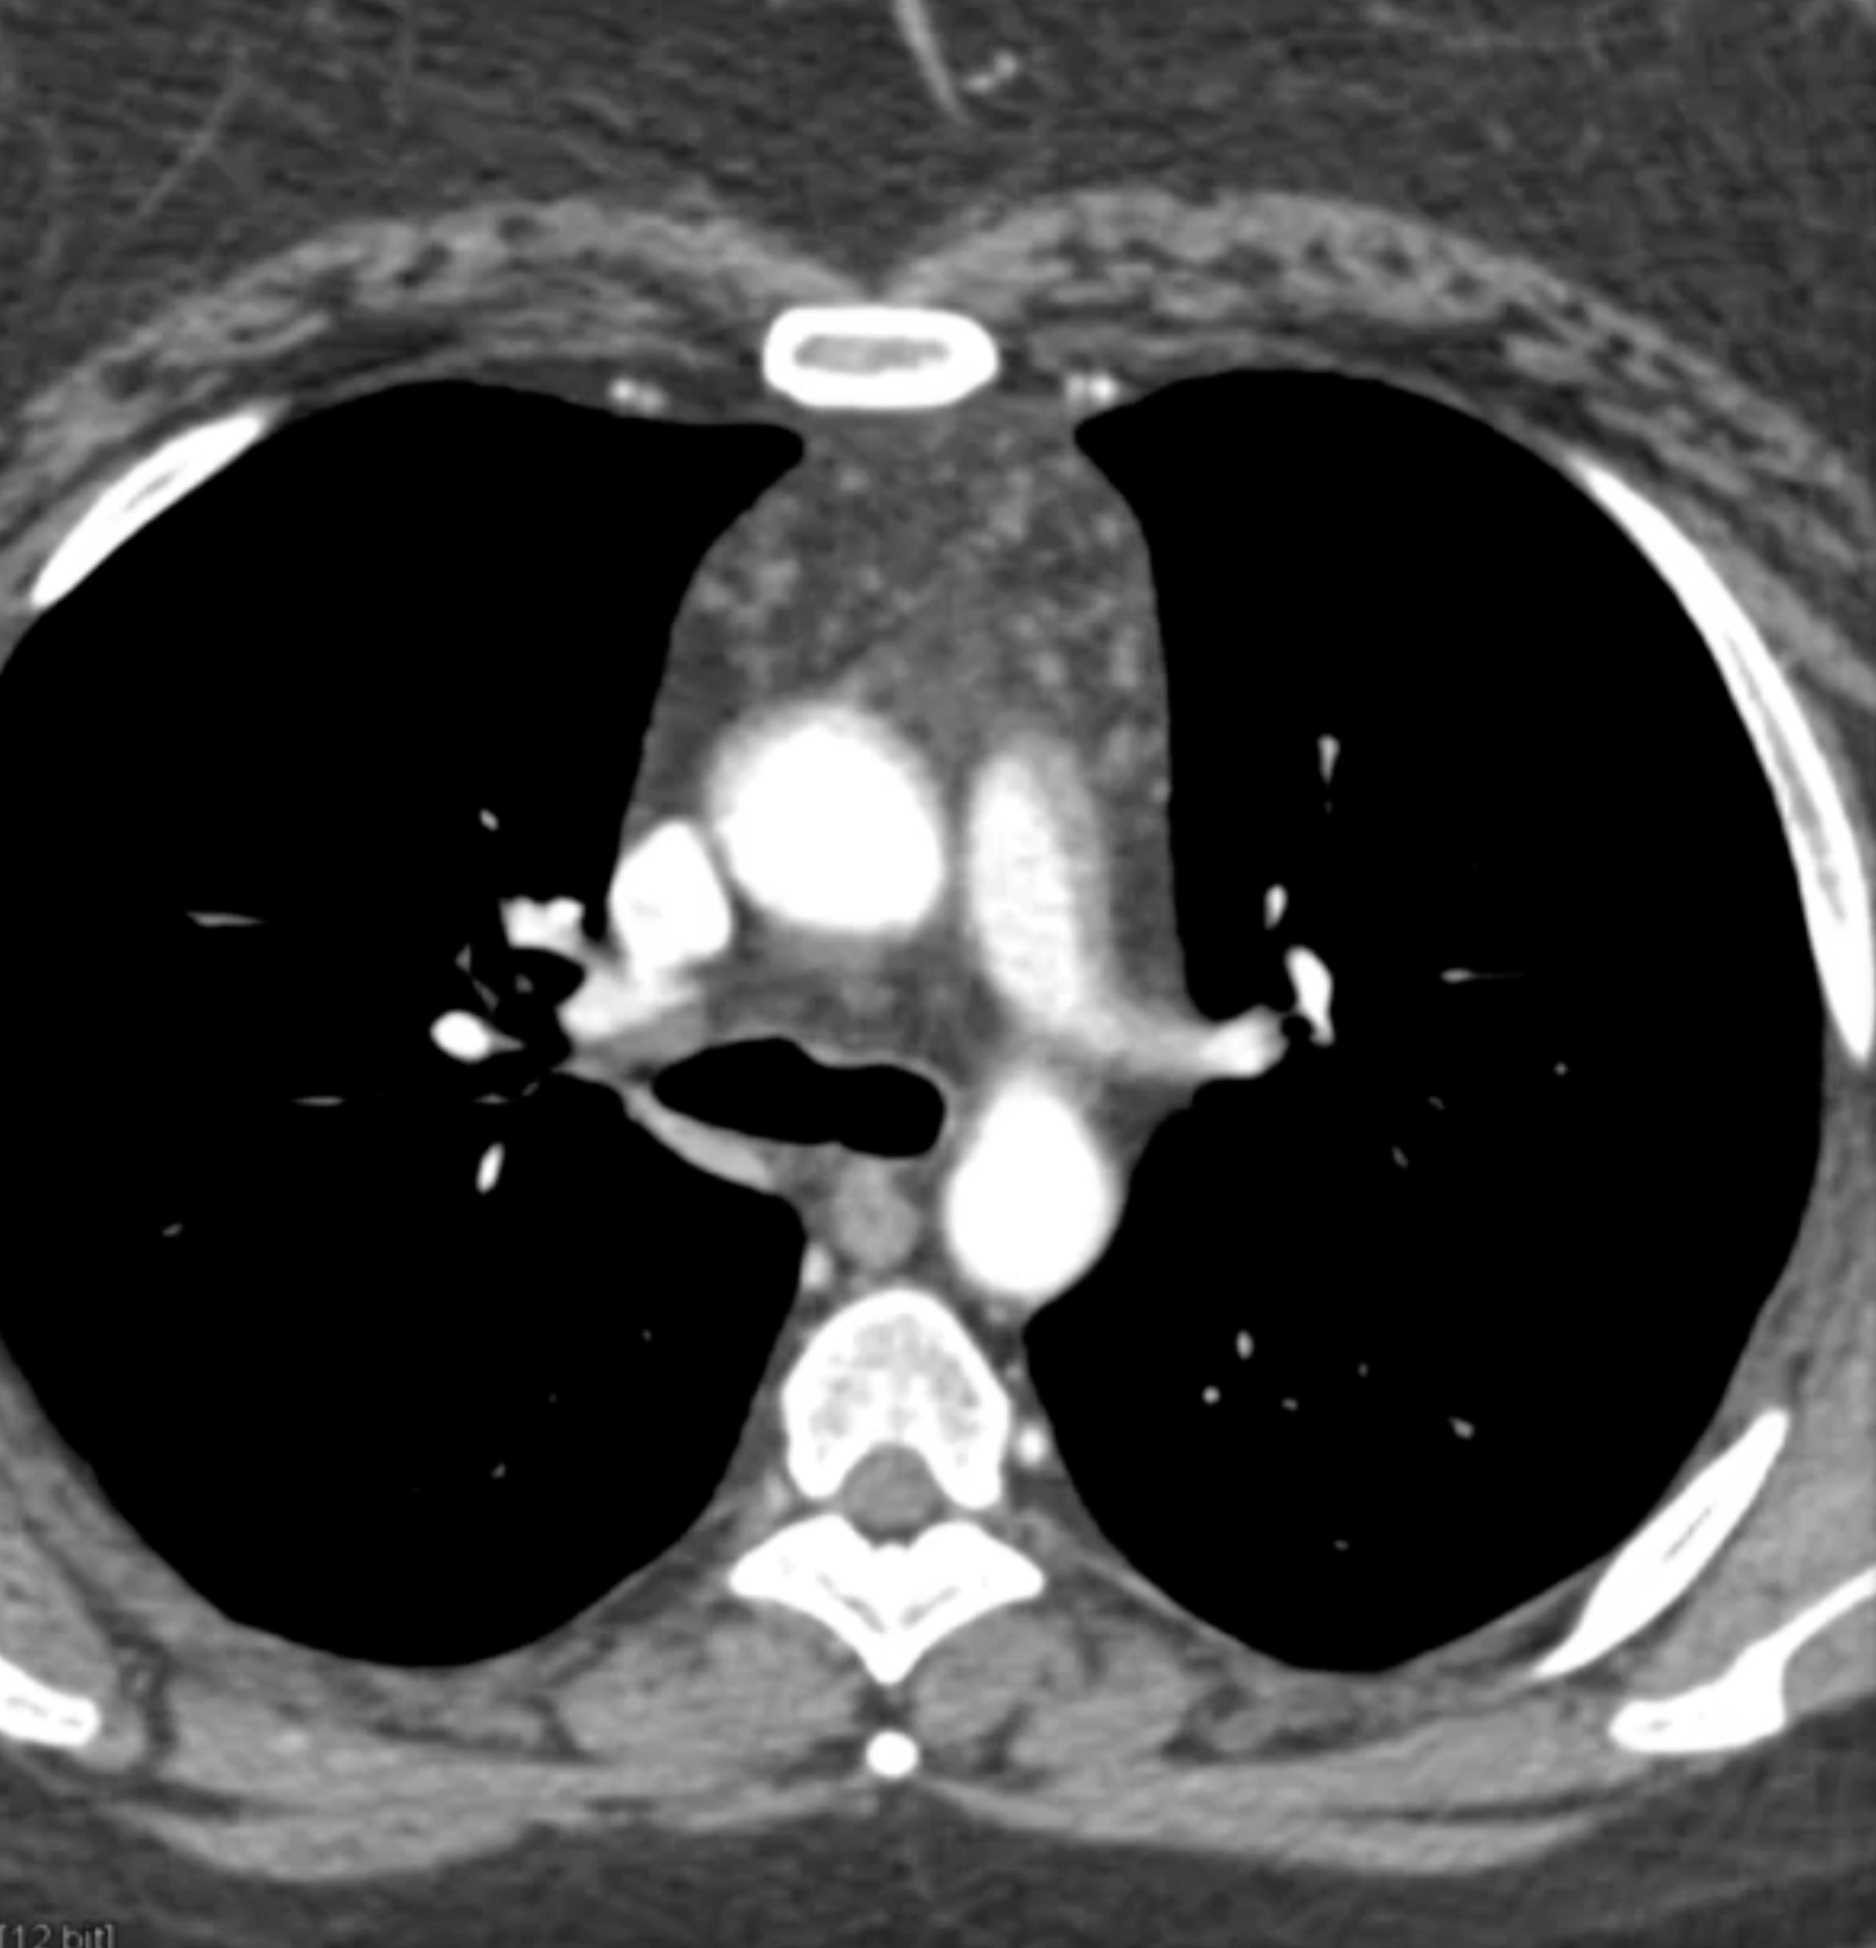

Thymolipoma